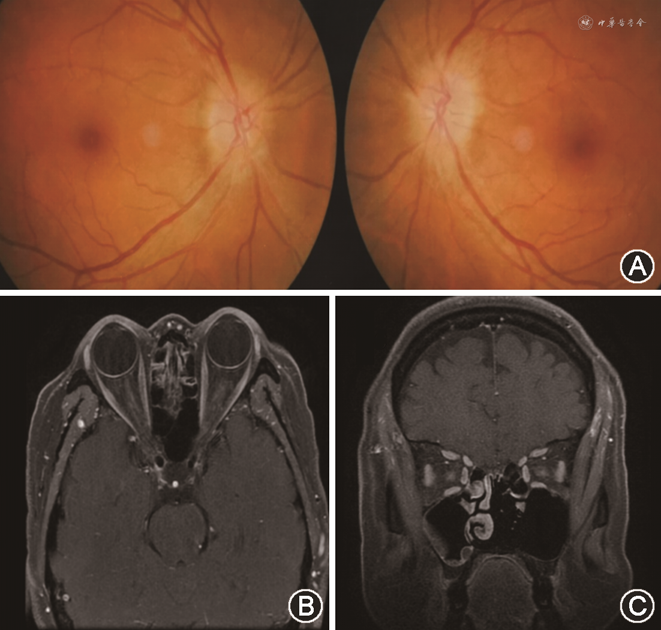

双侧ODS的主要病因的临床特征见表1,典型病例眼底及影像学表现见图2, 3, 4, 5, 6。

1. 颅内压增高:双侧ODS最常见的病因是颅内压增高(56/131,42.7%),其中IIH(43/56,76.8%)是PE最常见的病因。继发性颅高压(13例)的病因包括静脉窦血栓形成(cerebral venous sinus thrombosis,CVST)(7例)、上矢状窦旁脑膜瘤(1例)、脑囊虫病(1例)、硬脑膜动静脉瘘(1例)、中毒性脑白质病(1例)、结缔组织病(1例)、脑膜炎(1例)。

43例IIH患者中有32例女性、11例男性。仅有肥胖一项危险因素者13例,仅贫血者10例,仅静脉窦狭窄者7例,肥胖合并贫血者1例,肥胖合并静脉窦狭窄1例,无明确危险因素者11例。1例CVST患者为梅毒感染及心磷脂抗体阳性,其余患者未找到危险因素。